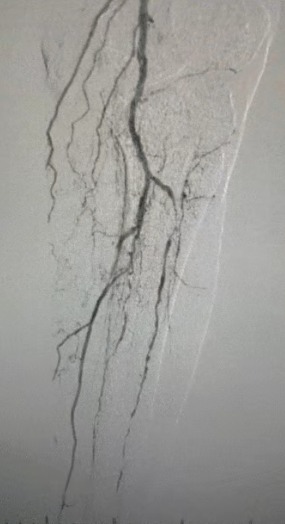

· Körperliche Untersuchung: Schwache Femur impulse; fehlende Popliteal-und Dorsalis-Pedis-Impulse; Geschwür am linken ersten Zeh; Nekrose am rechten ersten und zweiten Zehen

· Präoperative Bildgebung: Schwere, diffuse verkalkte Stenose in bilateralen Arterien der unteren Extremitäten

Chirurgisches Ergebnis

Nach dem Eingriff verbesserte sich die arterielle Stenose signifikant, der Blutfluss stieg und die Haut temperatur stieg. Es traten keine postoperativen Komplikationen auf. Sowohl der Patient als auch das Operations team waren mit den Ergebnissen sehr zufrieden.